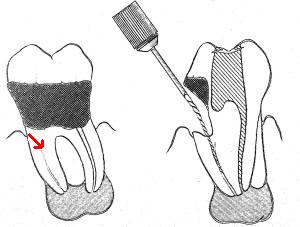

4- Grado de deterioro de la corona clínica por exposición

a caries o trauma

Grandes obturaciones cercanas a la cámara pulpar,

en la mayoría de las veces es directamente proporcional al

grado de calcificación de la cámara y de los conductos

radiculares. Ver primer imagen derecha

La falta de la corona clínica puede ser causa de

perforaciones accidentales. Ver segunda imagen derecha

La utilización sistemática de la radiografía periapical

pre-operatoria evitaría estos accidentes que suelen ser

comunes durante la práctica clínica.